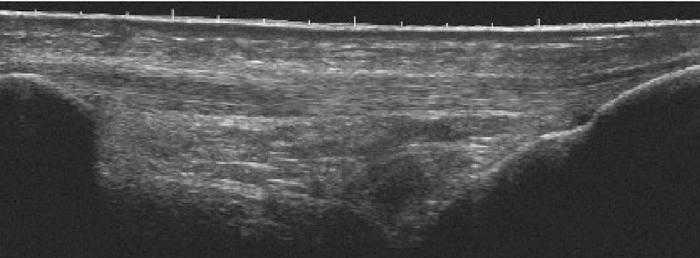

La rotura parcial reciente de las fibras del ligamento lateral de la rodilla (esguince de grado II) origina dolor intenso e incapacidad para conseguir la extensión articular completa. Pero cuando se trata como en este caso de una rotura ligamentosa producida 3 meses antes de la exploración, la sintomatología desaparece. Mediante exploración ecográfica, el equipo E-A permite valorar la integridad de los 2 fascículos del ligamento (fig. 7A) aunque detecta una pequeña imagen hipoecoica en un área del fascículo profundo22,35,36. Sin embargo, la exploración con el E-B permite observar una amplia zona hipoecoica de aspecto heterogéneo en el fascículo profundo del ligamento lateral interno, justo por encima de la cortical del cóndilo femoral. (fig. 7B)

Figura 7 A) Con el equipo E-A se observa la integridad del ligamento lateral interno con una pequeña imagen hipoecoica en el fascículo profundo, mientras que con el equipo E-B (B) se observa el fascículo profundo del mismo ligamento con un aspecto heteroecoico que corresponde a la zona de reparación justo por encima de la cortical ósea del fémur.